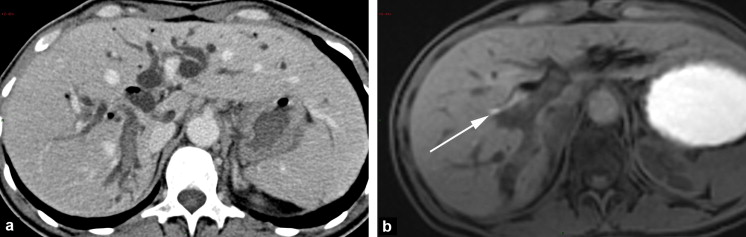

A:HPVG

B:pneumobilia

(Grainger & Allison's Diagnostic Radiology)